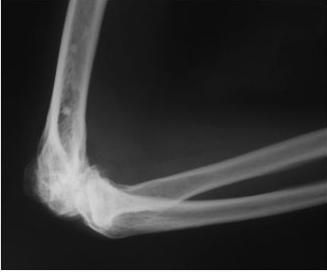

Диагностика

При возникновении болей в суставе самое лучшее, что может сделать человек, — это обратиться к врачу для того, чтобы выяснить причину появления боли. Несмотря на такое огромное количество причин болей в локте, диагноз в подавляющем большинстве случаев поставить несложно.

Уже в ходе беседы с пациентом доктор сделает предположения относительно характера патологии, опираясь на данные анамнеза (обстоятельства возникновения болей и т.д.), особенности болевых ощущений. Осмотр и пальпация (ощупывание) помогут подтвердить наличие того или иного заболевания, травмы.

Дальнейшее обследование будет назначено, исходя из предполагаемого диагноза:

- рентгенологическое исследование;

- пункция сустава с цитологическим исследованием пунктата (оценивают клеточный состав полученной жидкости);

- УЗИ суставов;

- артроскопия (визуализация полости сустава с применением специальной эндоскопической техники),

- которая дополняет пункцию сустава;

- компьютерная и магнитно-резонансная томография;

- лабораторные исследования при подозрении на подагру, ревматоидный артрит и др.